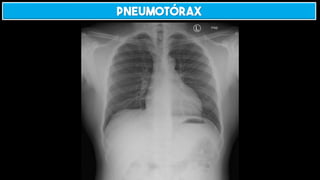

HEMOTÓRAX E PNEUMOTÓRAX

SINAL DO SULCO PROFUNDO

PNEUMOTÓRAX + PACIENTE SUPINO → SULCO PROFUNDO

Pneumotórax